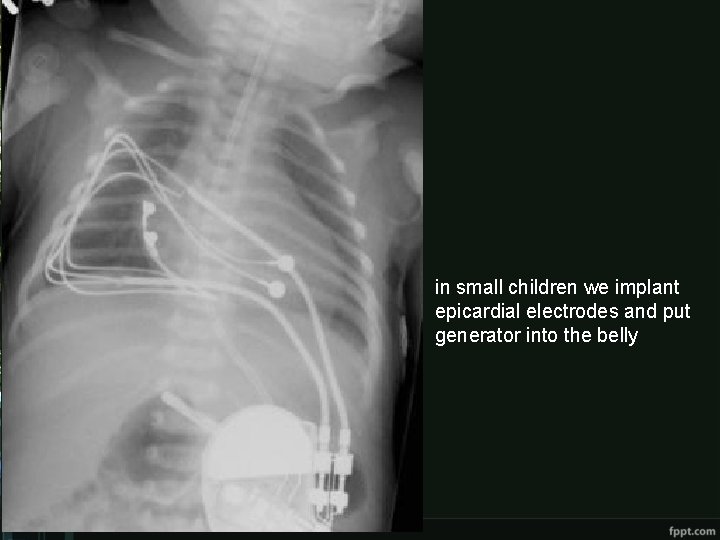

Treatment • pharmacological - euphyllin • pacemaker

in small children we implant epicardial electrodes and put generator into the belly